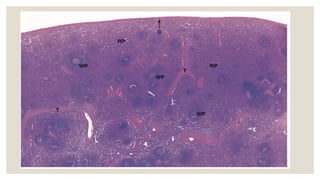

◦ White pulp consists

of lymphocytes and

lymphatic nodules

with a germinal

center, and a central

artery .

◦ Surrounded the

white pulp is the red

pulp, primarily

composed of venous

sinuses and splenic

cords .

HISTOLOGY ◦ The spleenis surrounded by a dense connective tissue capsule, from which arise connective tissue trabeculae. ◦ Located within the trabeculae are trabecular arteries and trabecular veins . ◦ Spleen is divided into white pulp and red pulp . ◦ Spleen is characterised by numerous lymphatic nodules that constitute the white pulp , included in the white pulp are the germinal centers and blood vessels called central arteries. ◦ Periarterial lymphatic sheaths (PALS) form the lymphatic nodules of the white pulp. ◦ The diffuse cellular meshwork that makes up the bulk of the organ and constitutes the red or splenic pulp. ◦ Present in the red pulp are the pulp arteries, venous sinuses and splenic cords( of billroth).

◦ White pulp:- ◦The lymphatic nodule exhibits a peripheral zone — periarterial lymphatic sheath with densely densely packed small lymphocytes. ◦ Central artery in the lymphatic nodule has a peripheral or eccentric position, however the artery occupies the center of the PALS, it’s called the central artery. ◦ The cells in the PALS are mainly T cells. ◦ Germinal center present. ◦ Red pulp :- ◦ Contains the splenic cords (of billroth) and venous sinuses . ◦ Splenic cords – contain small lymphocytes, various blood vessels. ◦ Venous sinuses– are dilated vessels lined with modified endothelium. ◦ Pulp arteries – branches of the central artery.

◦ White pulpconsists of lymphocytes and lymphatic nodules with a germinal center, and a central artery . ◦ Surrounded the white pulp is the red pulp, primarily composed of venous sinuses and splenic cords .